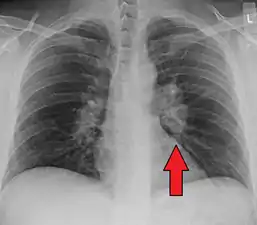

| Chest X-ray showing the typical nodularity of sarcoidosis, predominantly in the hila of the lungs. | |

Chest radiograph changes are divided into four stages:[105]

- bihilar lymphadenopathy

- bihilar lymphadenopathy and reticulonodular infiltrates

- bilateral pulmonary infiltrates

- fibrocystic sarcoidosis typically with upward hilar retraction, cystic and bullous changes

Although people with stage 1 radiographs tend to have the acute or subacute, reversible form of the disease, those with stages 2 and 3 often have the chronic, progressive disease; these patterns do not represent consecutive "stages" of sarcoidosis. Thus, except for epidemiologic purposes, this categorization is mostly of historic interest.[28]

Hilar adenopathy especially on the person's left (AP CXR)